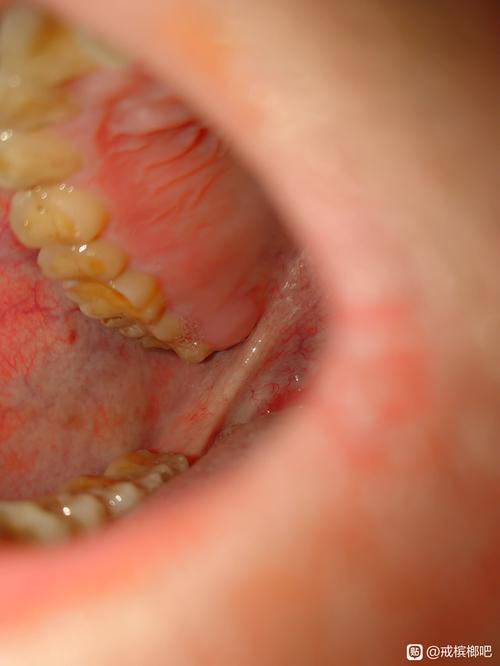

(图片来源网络,侵删)